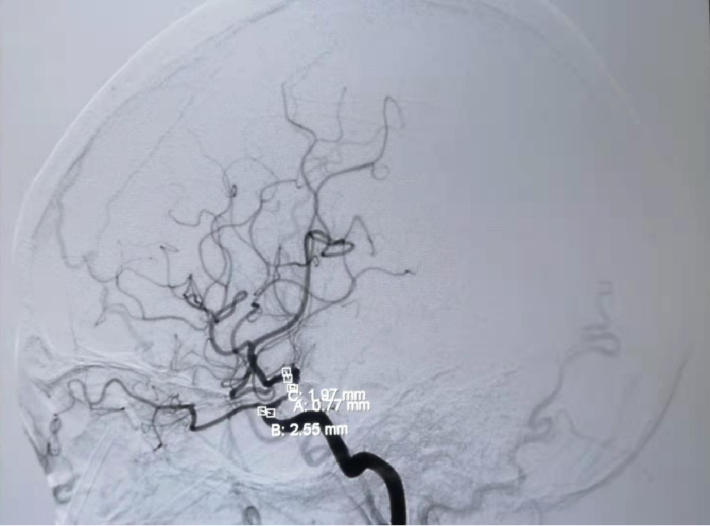

考虑狭窄段为夹层样改变,多角度导引导管造影,以更清晰地区分真假腔,选择最佳工作角度

--DSA显示左侧颈内虹吸段狭窄约72%。前交通开放,右侧大脑前动脉通过前交通动脉向左侧大脑前动脉、大脑中动脉供血区有代偿供血。

✔术中要点:左侧颈内动脉虹吸段狭窄考虑为夹层,予反复多个角度导引导管造影,以明确真假血管腔,微导丝通过狭窄段血管时谨慎、轻柔操作,务必判断导丝应从真腔通过。先予球囊扩张,观察扩张后狭窄段血管管径恢复情况。释放前准确定位支架近端,远端,应完全覆盖狭窄血管段。